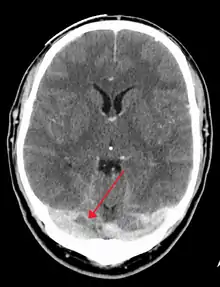

Computed tomography, with radiocontrast in the venous phase (CT venography or CTV), has a detection rate that in some regards exceeds that of MRI. The test involves injection into a vein (usually in the arm) of a radioopaque substance, and time is allowed for the bloodstream to carry it to the cerebral veins – at which point the scan is performed. It has a sensitivity of 75–100% (it detects 75–100% of all clots present), and a specificity of 81–100% (it would be incorrectly positive in 0–19%). In the first two weeks, the "empty delta sign" may be observed (in later stages, this sign may disappear).[11] The empty delta sign is characterized by enhancement of the dural wall without intra-sinus enhancement.[6]